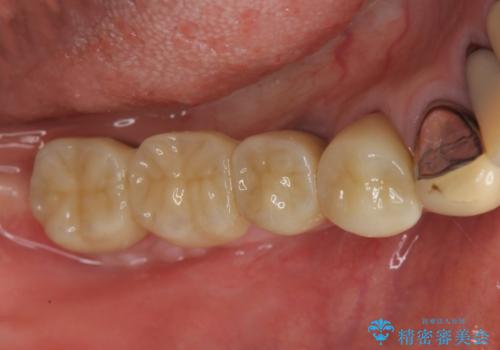

遊離歯肉移植術(硬い歯ぐきのインプラント周囲への移植)を行ったことで、炎症に強く歯ブラシのしやすい環境をインプラント周囲に整えることができました。

狭小な歯槽骨に対するインプラント治療

骨の造成、角化歯肉の移植を行いインプラント周囲の環境を整えた治療を計画します。